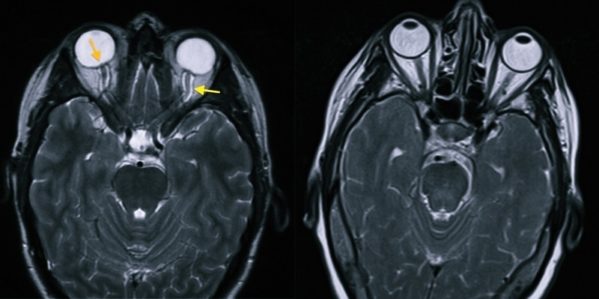

Внутричерепная гипотензия: КТ-исследования и их интерпретация

Раздел: Образы вокруг